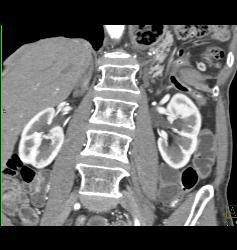

Diagnosis

Pancreas Divisum of Miniip